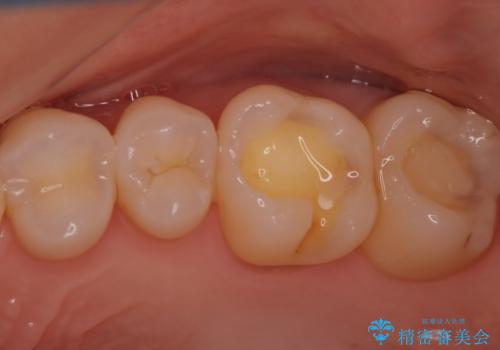

- 奥歯の銀歯が目立つということで来院されました。もともと入っていた銀歯を取り、虫歯の治療を行い、型取りを行ないます。

よく銀歯の下が虫歯になっていることがあります。

今回の患者様も銀歯を取ってみたら大きな虫歯になっていました。

虫歯をとり、銀歯から白いセラミックになったためかなり喜んでいただきました。